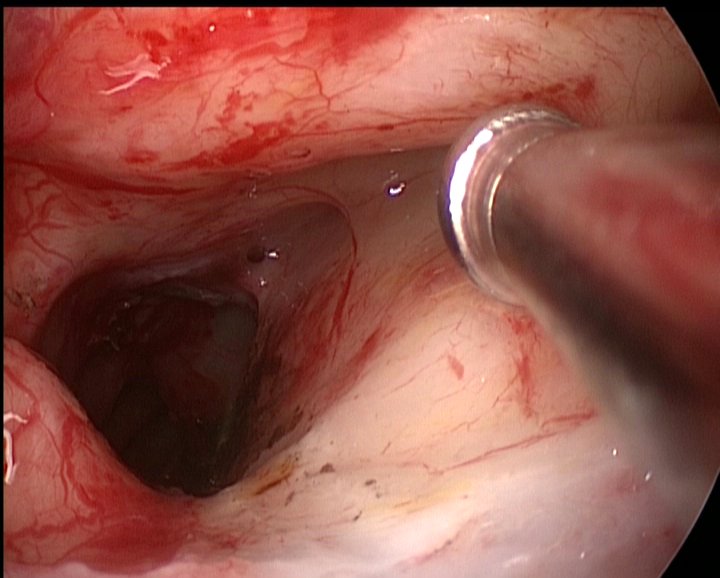

Se ablează macroscopic complet formaţiunea tumorală, frezarea zonei de implantare tumorală (tavan etmoidal – perete lateral al canalului nazofrontal stâng) şi cauterizarea acesteia în scop oncologic şi hemostatic (radiofrecvenţă, monopolar, fulguraţie 7-10W) – fig 4.

Fig 4: a – control endoscopic transnazal la finalul interventiei; b – control endoscopic extern – canal nazofrontal